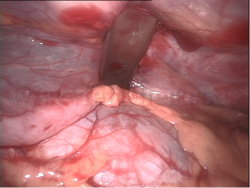

Técnica de Nuss